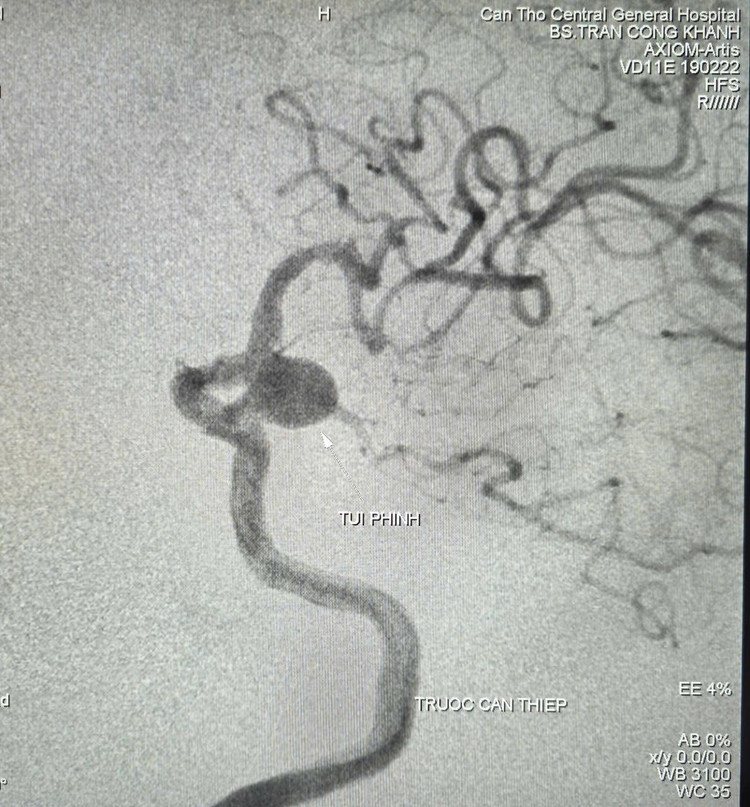

Hình ảnh túi phình trên phim chụp - Ảnh BVCC

Kết quả chụp cắt lớp vi tính và cộng hưởng từ cho thấy nhiều tổn thương cũ vùng não, túi phình đoạn gốc động mạch cảnh trong - thông sau bên trái, kích thước 9,2mm x 12mm, túi phình đang phát triển qua thời gian theo dõi (nguy cơ vỡ trong 5 năm khoảng 17.8%, ước lượng theo thang điểm PHASE 12 điểm ).

Sau khi hội chẩn đa chuyên khoa và dựa trên các khuyến cáo, cân nhắc giữa lợi ích và nguy cơ, ê-kíp quyết định tiến hành chụp mạch số hóa xóa nền (DSA) và can thiệp nội mạch nút túi phình, giúp bệnh nhân hạn chế nguy cơ vỡ gây đột quỵ, xuất huyết.